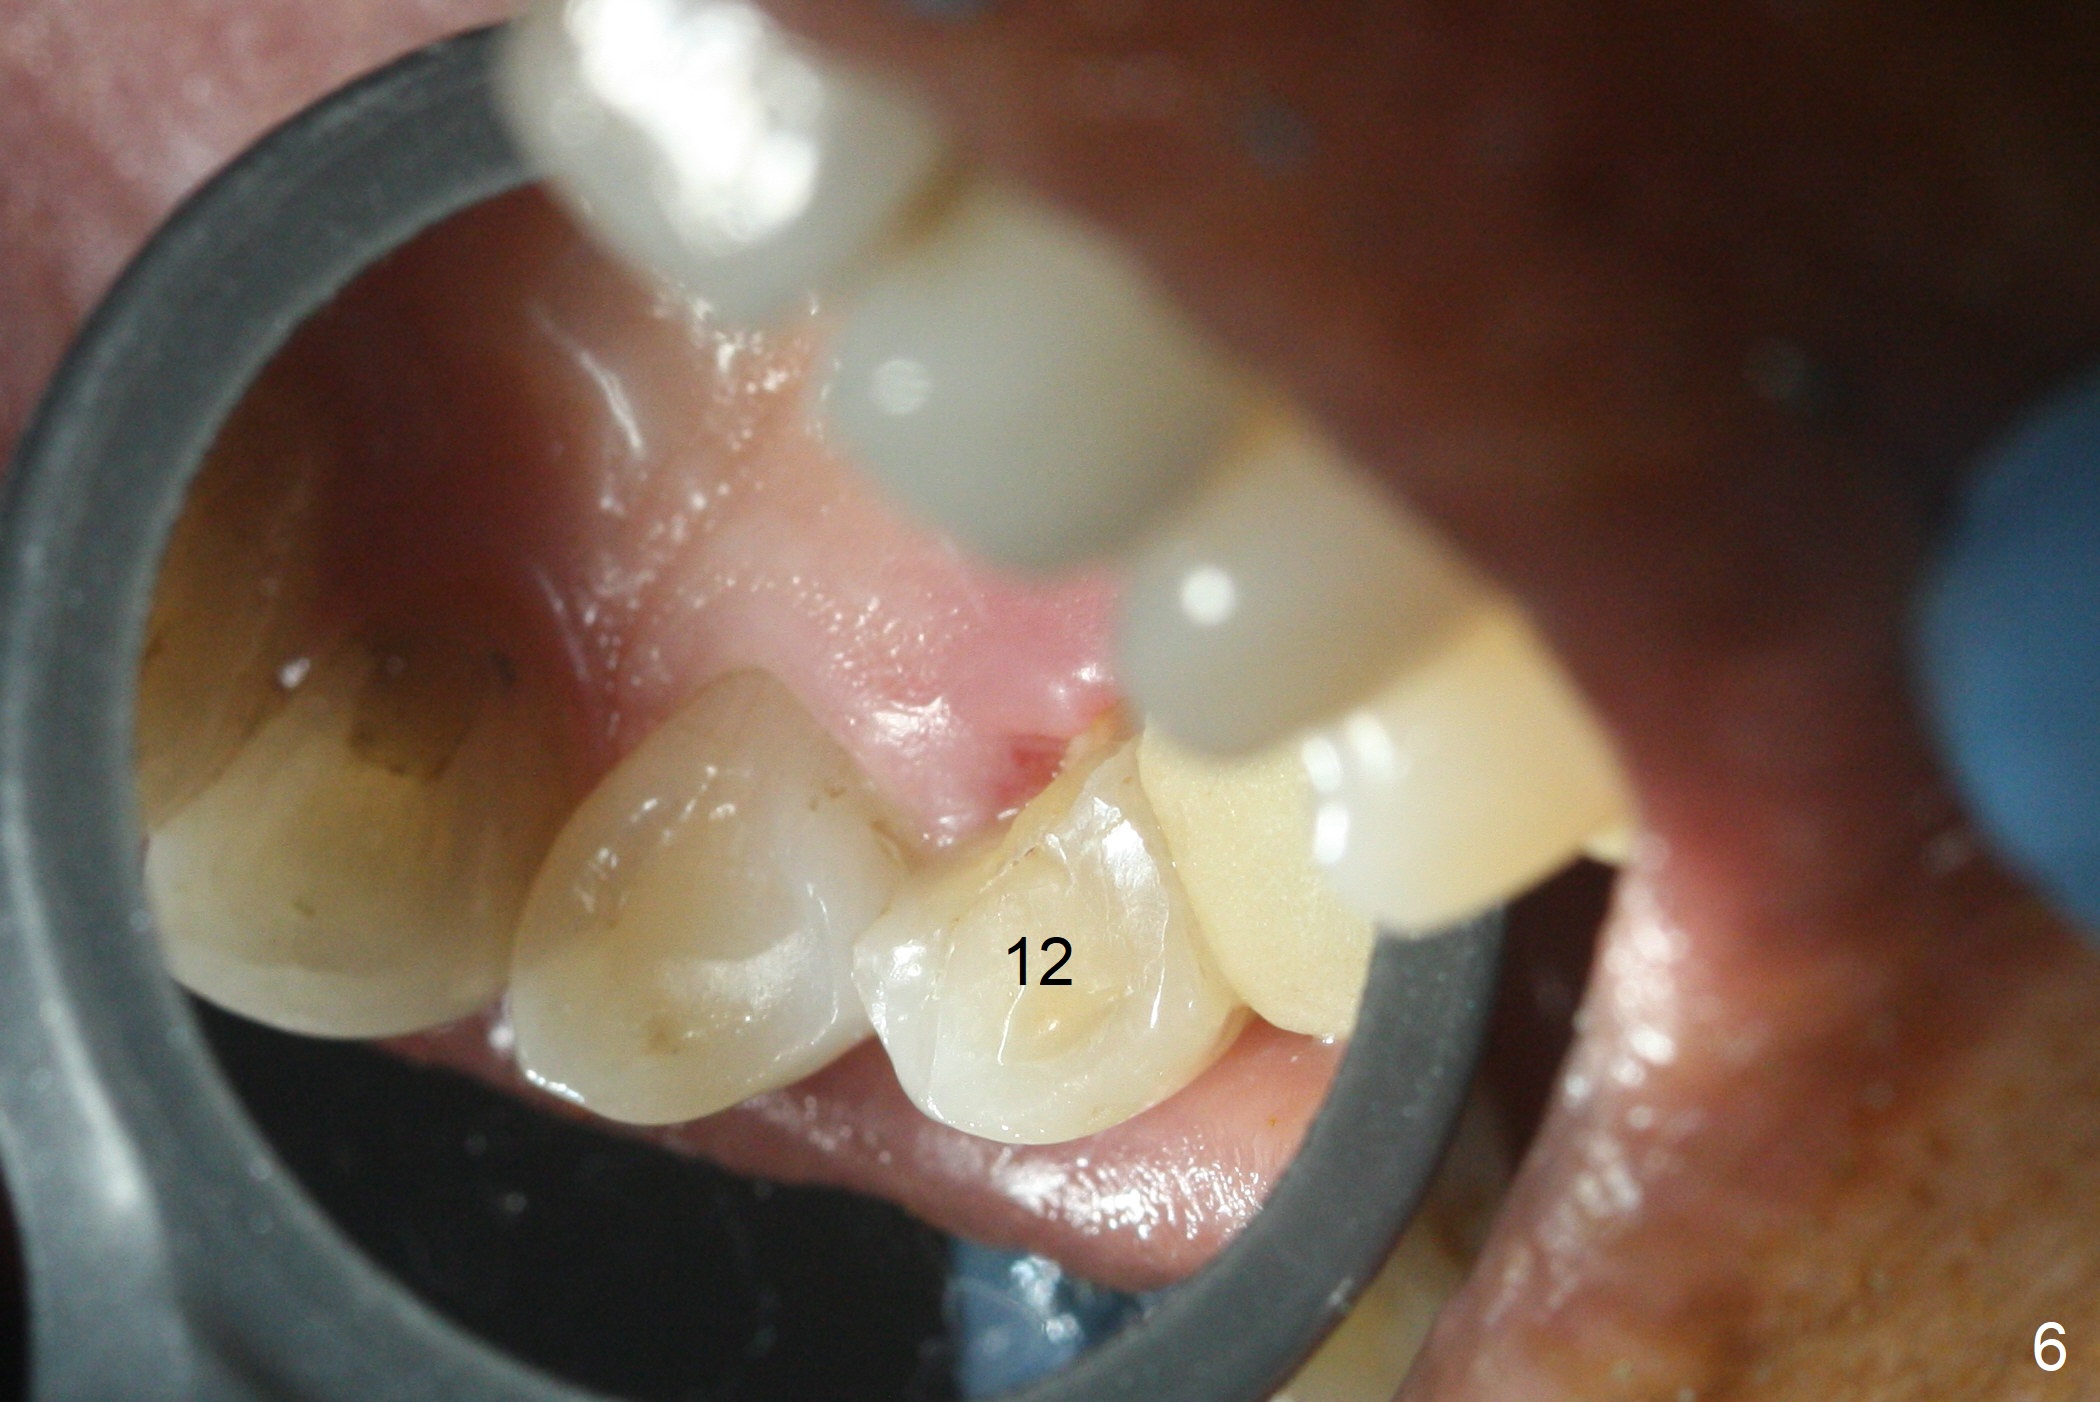

Preop photo shows palatally subgingival fracture (Fig.6). Initial depth is 15 mm at #12 after extraction (Fig.7) and then is extended to 17 mm. In fact the osteotomy is created in the palatal socket, since the septum is thin, while the buccal socket has its apical perforation. A 3.8x13 mm implant is placed (Fig.8); a 4.5x4(3) abutment and allograft are placed (Fig.9 *) prior to immediate provisional fabrication.